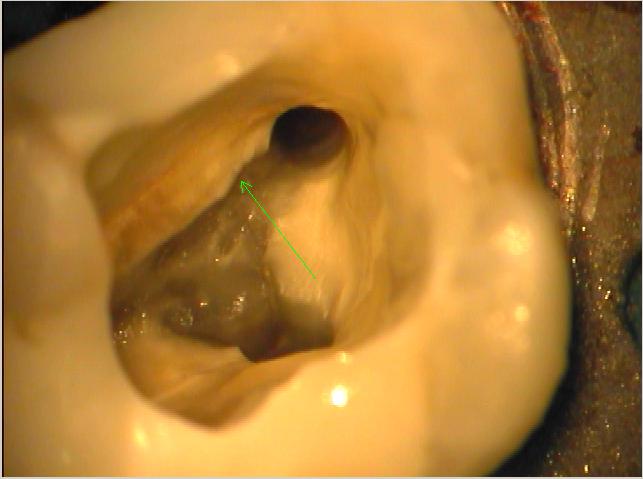

Situation vergrößert

Die gleiche Situation vergrößert. Der grüne Pfeil zeigt den winzigen oftmals nur zu erahnenden bzw. zu ertastenden Eingang von MB2